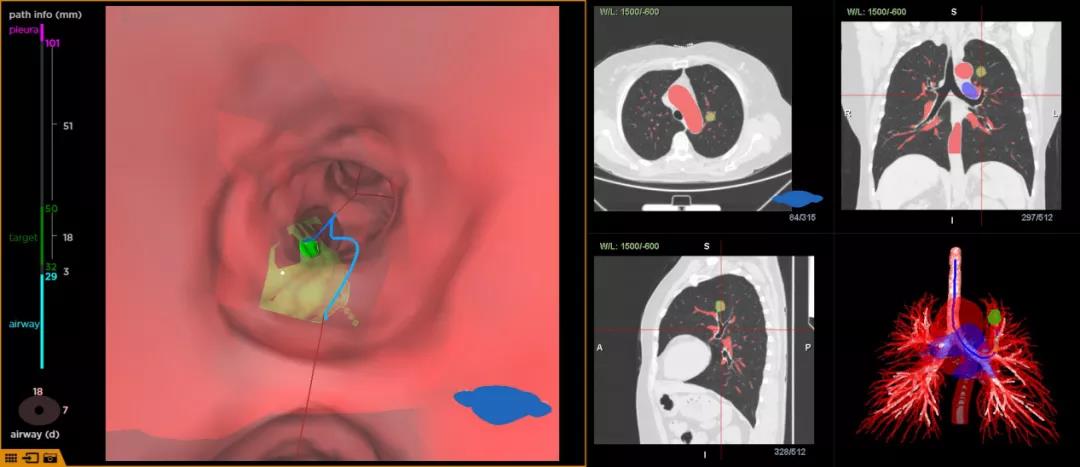

将CT数据导入LungPro全肺诊疗导航系统后,系统自动重建全肺血管气管,通过LungPro系统精准识别病灶,明确病灶位于左上叶尖端亚段支开口,病灶临近气道,旁边伴行两根大血管;且明确病灶整体大小,及其与气道、血管的位置关系等后,确定手术方案。

在LungPro全肺诊疗导航系统的气道内导航模块引导下,实时显示镜下视野及路径信息,快速精准抵达病灶,整个手术仅耗时不到五分钟。使用径向超声确认抵达病灶中央,并行活检钳取得肺活检组织。经现场ROSE判定为非正常肺组织。

王主任对LungPro全肺诊疗导航予以充分肯定。术前规划、术中匹配操作简单,特别是LungPro全肺诊疗导航的气道内导航模块,能快速精准引导支气管镜抵达病灶、且没有任何定位耗材,独有的3D重建全肺血管、气管技术,为临床诊断和治疗提供更安全有效的手术方案。